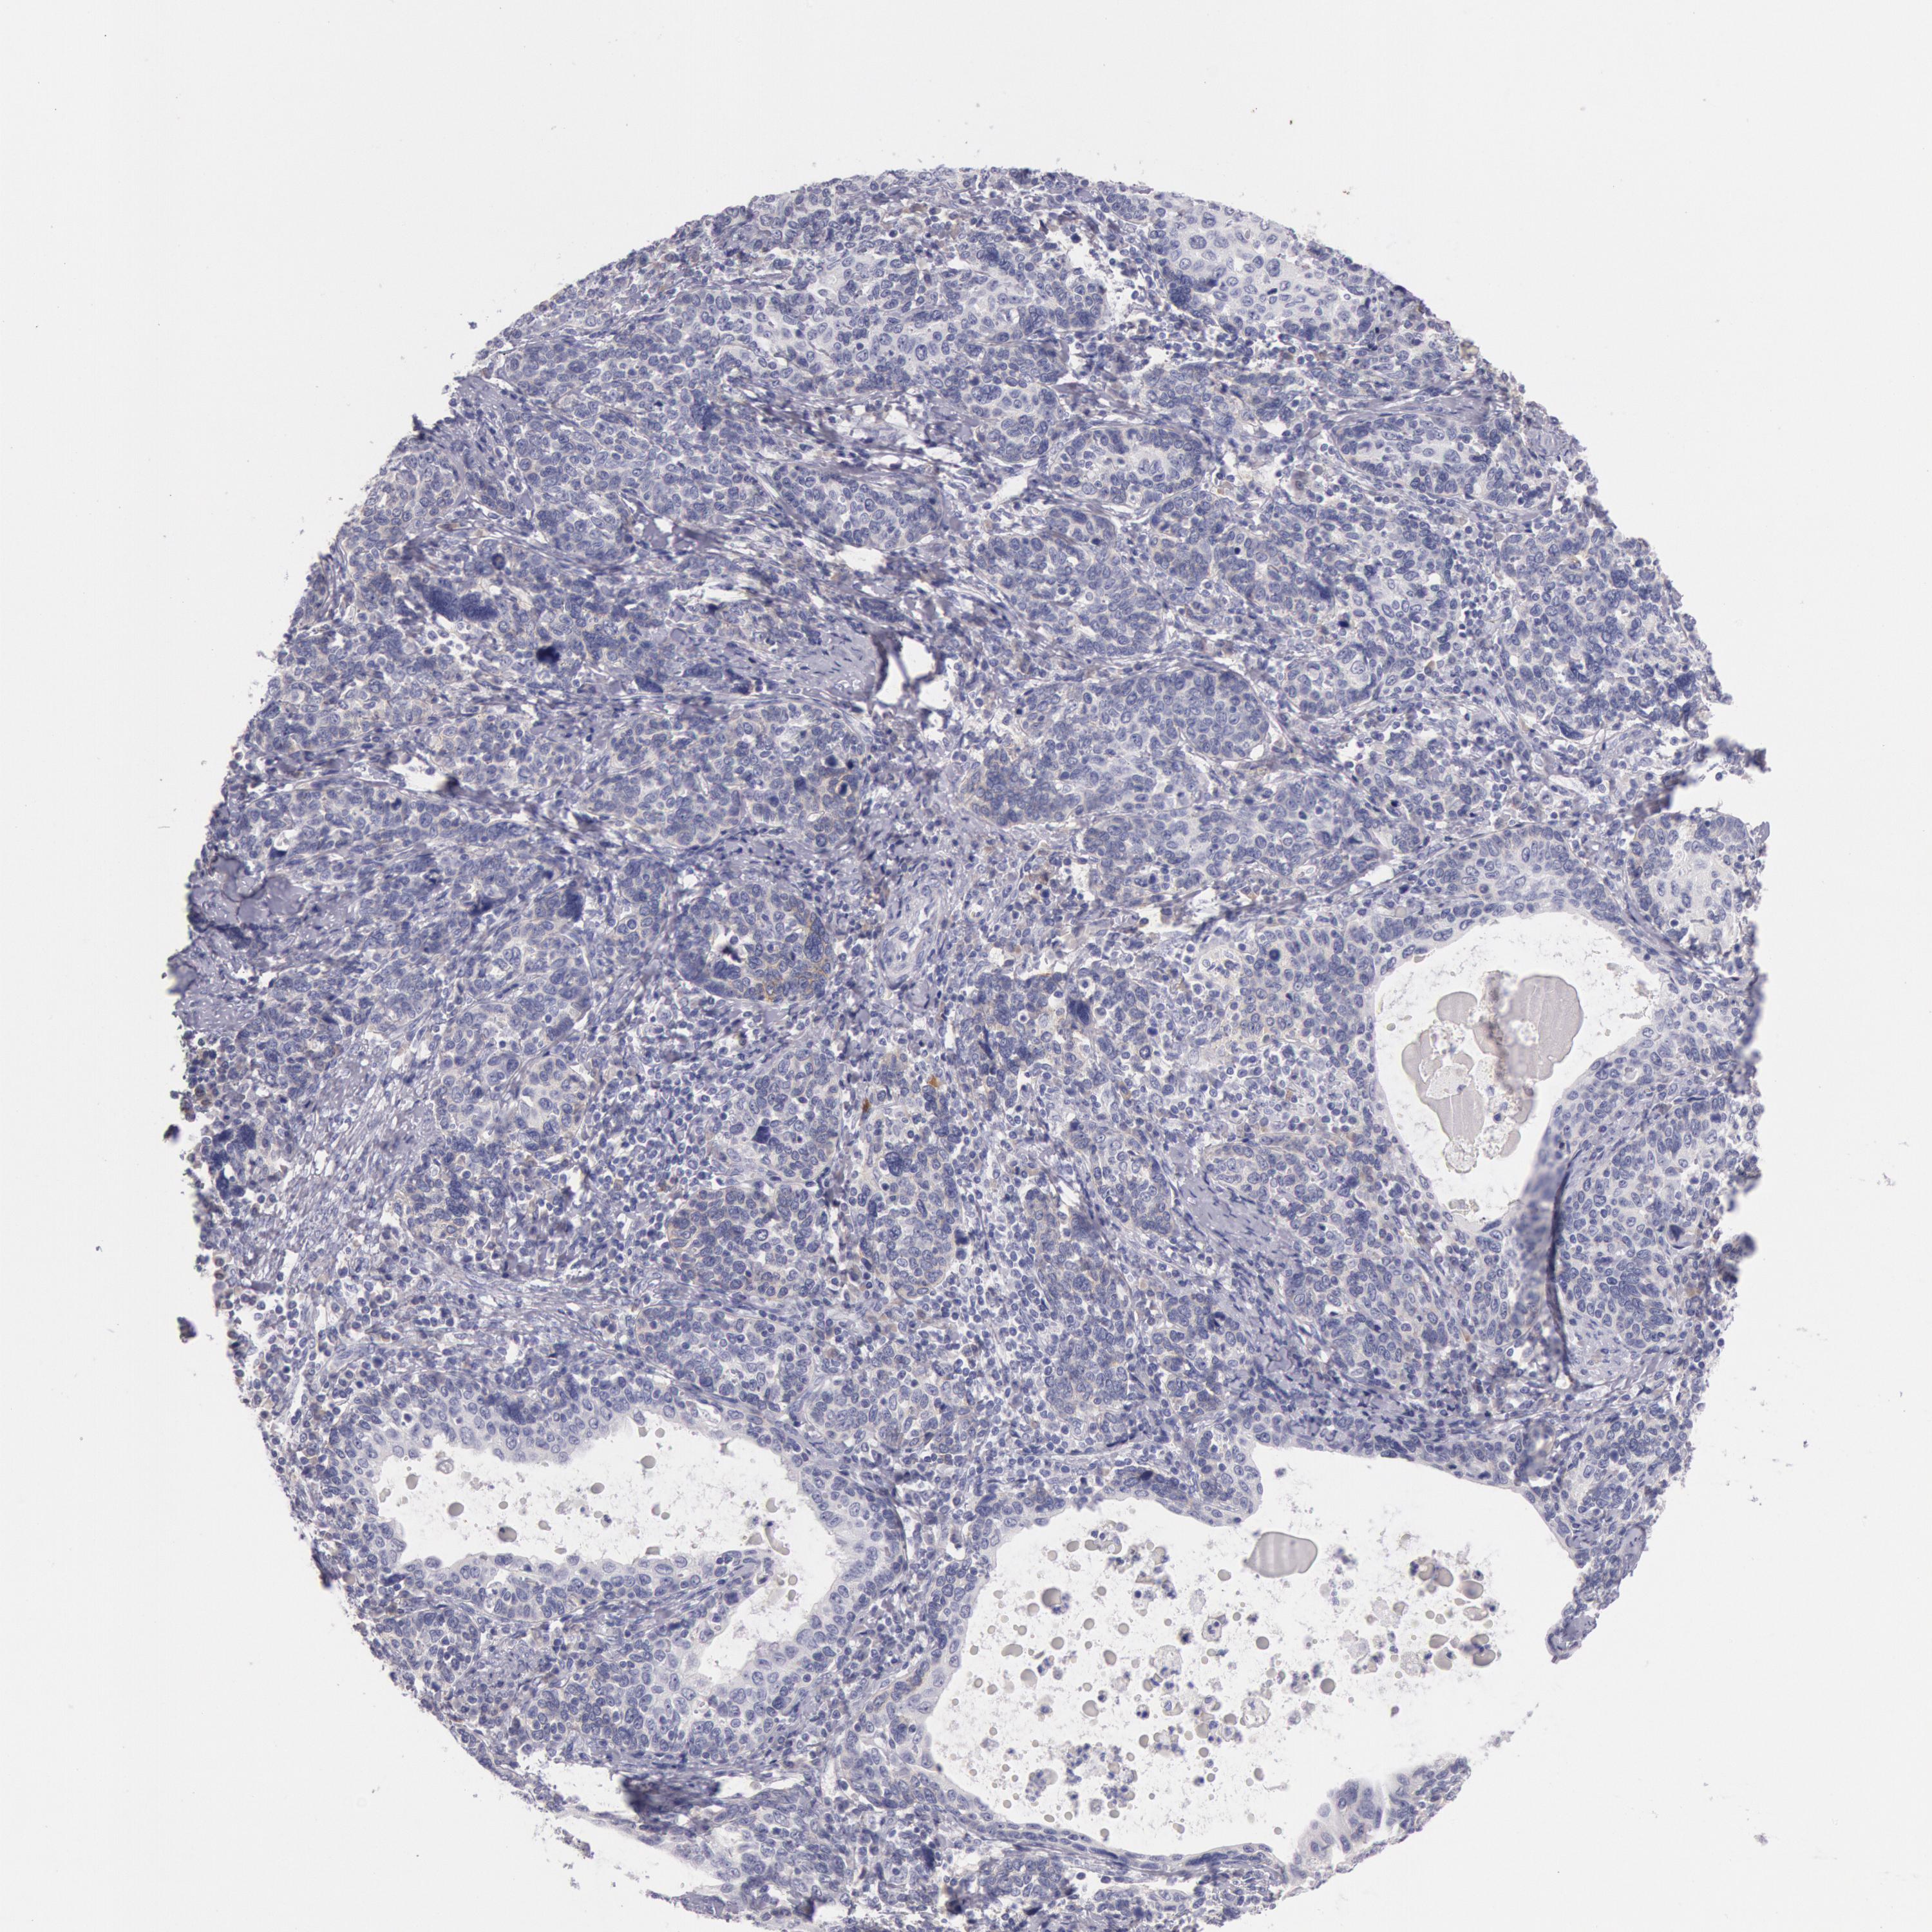

CERVICAL CANCER - Protein expressioni

A mouse-over function shows sample information and annotation data. Click on an image to view it in a full screen mode. Samples can be filtered based on level of antibody staining by selecting one or several of the following categories: high, medium, low and not detected. The assay and annotation is described here.

Note that samples used for immunohistochemistry by the Human Protein Atlas do not correspond to samples in the TCGA dataset.

Antibody stainingi

Antibody staining in the annotated cell types in the current human tissue is reported as not detected, low, medium, or high, based on conventional immunohistochemistry profiling in selected tissues. This score is based on the combination of the staining intensity and fraction of stained cells.

Each image is clickable and will lead to virtual microscopy that enables deeper exploration of all samples and also displays staining intensity scores, fraction scores and subcellular localization as well as patient and tissue information for each sample.

Adenocarcinoma, NOS

Squamous cell carcinoma, NOS